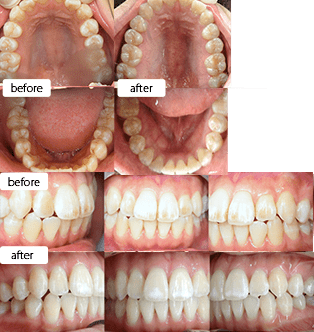

治療方法 【矯正】インビザライン、光加速装置「PBM HEALING」

【ホワイトニング】

ホワイトエッセンスコース

(オフィスホワイトニング※1 3回、ホームホワイトニング 2か月分、クリーニング※2 2回、特選ホームケア用品)治療の説明 主訴: 前歯が出てる、下の歯のがたつき 年齢 24歳 ![]()

治療費用 1,054,000円(税込)、相談・検査・診断料・調整料:無料 治療期間 【矯正】1年10か月 通院回数 【矯正】 18回

【ホワイトニング】期間・回数:治療内容により異なります治療の副作用(リスク) 【矯正】咬合痛、歯根吸収、歯根露出が生じる可能性があります。

【ホワイトニング】個人差がありますが、施術中や施術後に歯がしみる場合があります。

保証制度:040 の白さに達成するまで追加で施術を受けられる制度です。万が一040 に達しない場合は、材料費を差し引いた70,000 円を返金します。

※テトラサイクリン薬剤による変色は保証の対象外です。

※差し歯等でない限り、右上の前歯が保証対象歯です。

中途解約制度:あり

※1 オフィスホワイトニング プロプラス

※2 オーラルスパクリーニング、ナノアパタイトコート研磨歯科医師からのコメント 頬側拡大を行い、上顎前歯の突出感を改善。追加アライナーでは残存空隙利用と少し遠心移動を追加して咬合を調整しています。